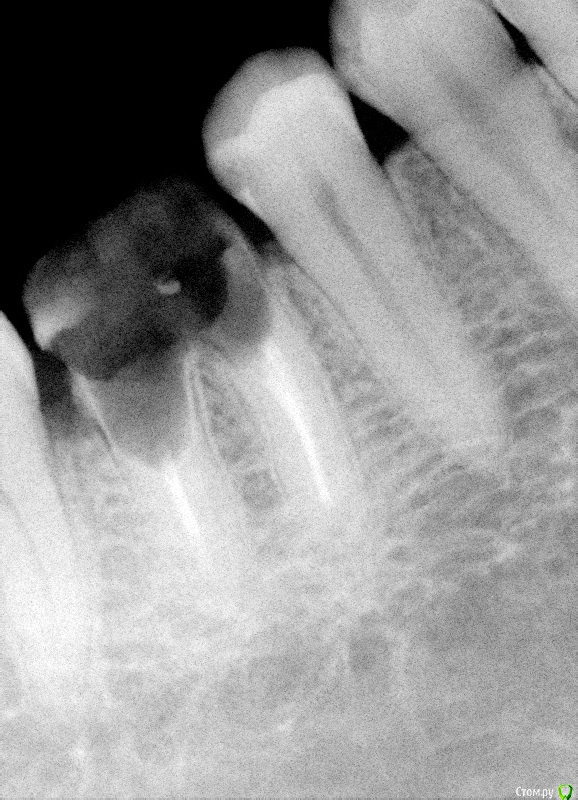

krokomot Опубликовано 26 февраля, 2015 Поделиться Опубликовано 26 февраля, 2015 Уважаемые коллеги есть сомнительный зуб который 10 лет разрушался под штампованной коронкой. Предложите варианты лечения, не учитывая эндодонтическое лечение. И стоит ли?! Всем спасибо за участие. после некрэктомии Щадящей! Ссылка на комментарий

krokomot Опубликовано 26 февраля, 2015 Автор Поделиться Опубликовано 26 февраля, 2015 Тем неменее перфорций стенок нет, полноценная только вестибулярная стенка разделения корней нет, устойчив. не беспокоил. Удалить проблем нет, как вы думаете возможно ли восстановление, если можно обосновывайте ответ. Хотел еще фото с внутри ротовой но ассистент удалил Ссылка на комментарий

chervoncevdaniil Опубликовано 26 февраля, 2015 Поделиться Опубликовано 26 февраля, 2015 Тем неменее перфорций стенок нет, полноценная только вестибулярная стенка разделения корней нет, устойчив. не беспокоил. Удалить проблем нет, как вы думаете возможно ли восстановление, если можно обосновывайте ответ. Хотел еще фото с внутри ротовой но ассистент удалил Док,дефект ниже уровня кости,очень тонкие стенки,некачественное эндо,феррула тут и в помине нет,какие еще аргументы нужны?целесообразность сохранения такого зуба какая? 2 Ссылка на комментарий

krokomot Опубликовано 26 февраля, 2015 Автор Поделиться Опубликовано 26 февраля, 2015 (изменено) Док,дефект ниже уровня кости,очень тонкие стенки,некачественное эндо,феррула тут и в помине нет,какие еще аргументы нужны?целесообразность сохранения такого зуба какая?Спасибо за поддержку) Просто у пациента как низуб так сюрприз, везде где было эндо все оч плохо кстати в моем посте про каналонаполнители в 3-х каналах тоже его зуб. Изменено 26 февраля, 2015 пользователем krokomot 2 Ссылка на комментарий

krokomot Опубликовано 27 февраля, 2015 Автор Поделиться Опубликовано 27 февраля, 2015 Удаляйте лучше. Зачем вам проблемы с этим пациентом в будущем?Обновлено. Добавляю недостающее фото удалил после повторной ревизии обнаружилась перфа на дистальной стенке, ниже уровня устья. 1 Ссылка на комментарий